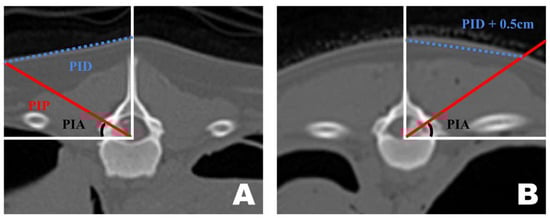

Preoperative CT-based PID measurements are generally reliable for guiding portal insertion. However, variations in body shape introduced discrepancies between the premeasured PID and the actual lateral distance on the skin surface during surgery (Figure 6). In dogs with shorter torsos and thicker paraspinal tissues, the premeasured PID did not fully reflect the true lateral distance required for portal insertion. By contrast, in thinner dogs with flatter dorsal contours, the CT-based PID values corresponded more closely to the actual skin distance. In cases with a curved dorsal surface, an additional lateral adjustment of approximately 0.5 cm was applied to the premeasured PID to achieve accurate portal placement.

Figure 6.

Differences in portal insertion distance (PID) measurement values in dogs with different body types as seen in the frontal view of a transverse computed tomography scan. (A) PID measurement in a thin-bodied dog. (B) PID measurement in a thick-bodied dog. Since the actual distance drawn on the skin differed during surgery, an additional 0.5 cm was added to the premeasured PID value for portal insertion.